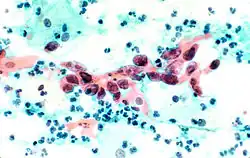

The stain should result in cells that are fairly transparent so even thicker specimens with overlapping cells can be interpreted.[2] Cell nuclei should be crisp, blue to black in color[12][13] and the chromatin patterns of the nucleus should be well defined. Cell cytoplasm stains blue-green and keratin stains orange in color.[13][5]

Eosin Y stains the superficial epithelial squamous cells, nucleoli, cilia, and red blood cells.[2] Light Green SF yellowish confers a blue staining for the cytoplasm of active cells such as columnar cells, parabasal squamous cells, and intermediate squamous cells.[14] Superficial cells are orange to pink, and intermediate and parabasal cells are turquoise green to blue.[12]

Squamous cell carcinoma in the cervix.

Squamous cell carcinoma in the cervix.